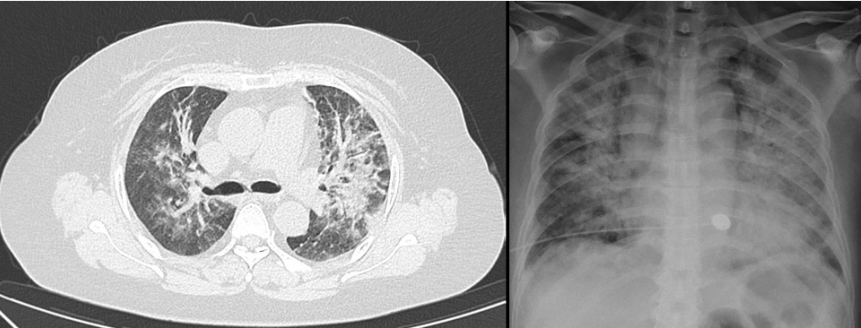

好发于用药后3个月,发热最常见,常是主要早期表现。呼吸道症状少,多以干咳为主,少见脓性痰。起病缓急差异极大,可以比较隐匿,也可突发起病,很快发展至严重呼吸衰竭,死亡率高。临床上常见的可快速进展至重症肺炎的病原体为耶氏肺孢子菌、巨细胞病毒、军团菌等。我中心曾收治一例成年女性患者,基础疾病为成人Still病,口服甲泼尼龙4个月,主诉“胸闷、呼吸困难4 d”,入住我院心内科,入院后诊断为“心衰”并进行相关处理,完善胸部CT检查可见双肺渗透性病变(图1),考虑呼吸困难原因为“肺部感染”,遂转入呼吸科治疗。转入呼吸科2天后,患者氧合迅速恶化,出现呼吸窘迫,氧合不能维持,于是转入RICU。转入当天再次复查胸部X线片发现双肺大面积渗出性病变(图1),最终诊断为PCP。该患者从发病到氧合不能维持行机械通气共7 d时间。另一例患者为中年男性,仓库保管员,以“发热”为主要诊断,入住血液科,基础疾病为初治的急性淋巴细胞白血病。入院第1天复查胸部CT可见右下肺少量片状渗出影(图2)。患者伴持续高热,予以常规抗G+菌及抗G-菌治疗,效果不佳。4 d后再次复查胸部CT发现肺部病变快速进展(图2)。患者出现严重呼吸窘迫,转入RICU。即刻完善气管镜检查,病原学提示军团菌,而此时患者已经出现极严重的呼吸窘迫,氧合不能维持,遂行气管插管接机械通气,最终病原学结果为军团菌。中年男性患者,基础疾病为肾病综合征,应用激素3个月,以“呼吸困难5 d”为主诉入院。胸部CT提示双肺弥漫性磨玻璃样渗出同时伴有大量结节(微小结节)(图3)。入院第2天紧急插管机械通气,最终病原学提示为巨细胞病毒感染。预测免疫受损宿主病死率的三个独立危险因素分别为:①疾病严重程度增加;②需要机械通气;③延迟诊断超过5 d以上。对于免疫受损宿主,早期诊断尤为重要,因其可以快速进展为重症ARDS。不同的氧合状况下,ARDS的诊疗策略不同。对于轻、中度ARDS,通常选择无创通气;对于中重度ARDS,通常以有创机械通气、俯卧位以及ECMO等进行呼吸支持。重症ARDS治疗的具体步骤和实施方法(简称“六步法”)如下: